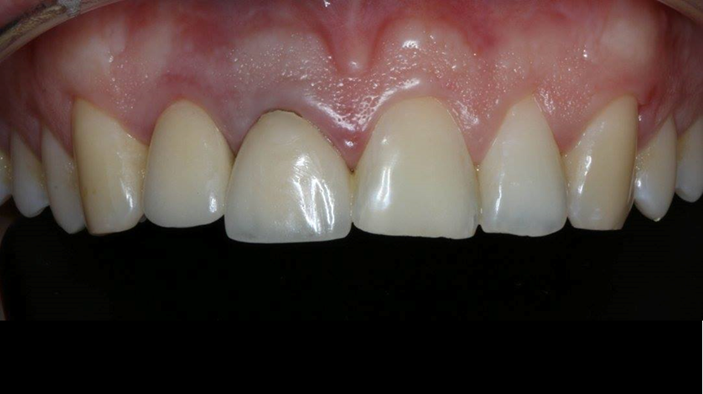

Clinical case: BPET PREDICTABILITY - State-of-the-Art SOCKET SHIELD

- Courtesy of Dr. Howard Gluckman, South Africa -

“AnyRidge is perfect for the anterior esthetic zone due to its strong initial stability & fast osseointegration.

Plus, KnifeThread® ensures space maintenance when using the PET/Socket Shield/Root Membrane Technique, showing excellent bone growth.”